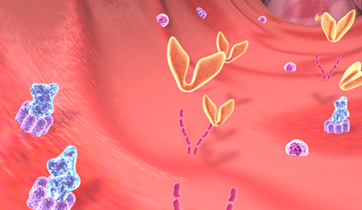

Natracor; hBNP MOA

Scios Pharmaceuticals

Adair Greene Advertising

Natracor treats congestive heart failure triggered by the renin - angiotensin - aldosterone system which causes sodium and fluid retention and vaso-constriction. hBNP is a regulatory hormone, which binds to Guanylate cyclase receptors to reverse effects.